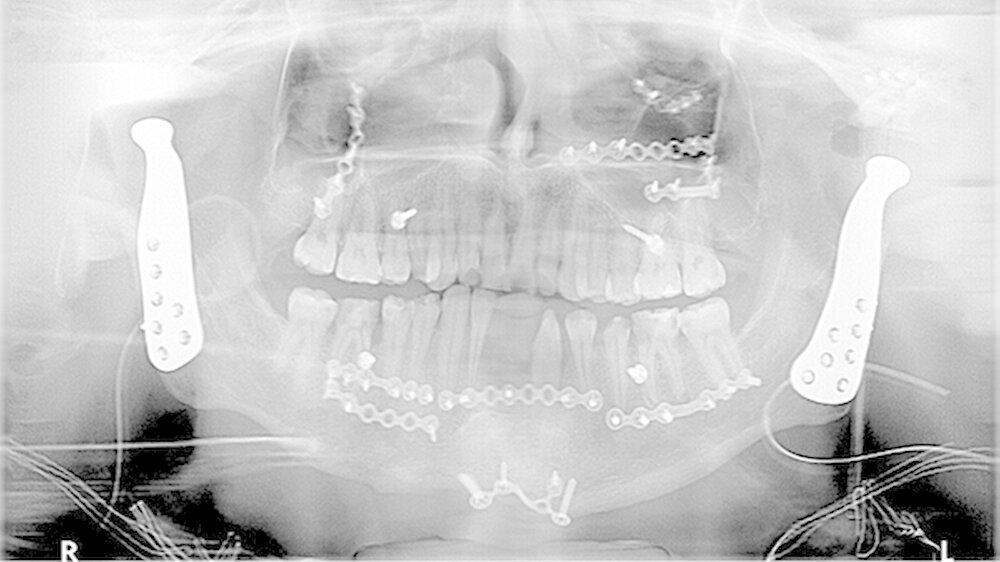

In der Folge entwickelte sich binnen fünf Monaten eine absolute Mundöffnungsbehinderung. Die SKD betrug null Millimeter. Passend zur klinischen Symptomatik zeigten sich radiologisch die Zeichen einer knöchernen Ankylose der Kiefergelenke beidseits Typ III nach Sawhney [1986] (Abbildung 1a-d).

Vor der definitiven Fixierung der Prothesen wurden Dummys als Test eingesetzt, um eine optimale Positionierung der passgenauen finalen Prothesen zu erreichen (Abbildung 2 bis 9). Abbildung 10 a und 10b zeigen die postoperative Röntgenkontrolle.